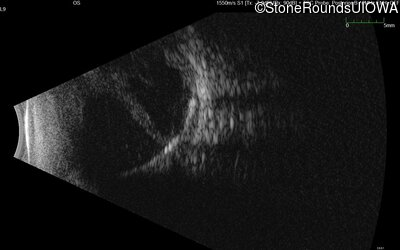

B-Scan Ultrasonography - Right - 20/300 sc

Exemplar